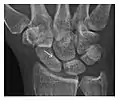

High-energy trauma fractures

Figure 3: A 26-year-old man presenting with wrist pain after being assaulted. (a) Initial anteroposterior radiograph shows a subtle linear lucency within the scaphoid extending to the scaphocapitate articular surface that was overlooked (arrow). (b) Initial "scaphoid" view was negative. (c) Followup anteroposterior radiographs, 12 days later, shows obvious scaphoid fracture (arrows).[1]

Triquetral fracture usually occurs on the dorsal aspect by impingement from the ulnar styloid or avulsion of strong ligamentous attachment. The dorsal avulsion fracture or "chip fracture" appears as a small bony fragment on the dorsal aspect of the triquetrum and is best detected on the lateral view(Figure 4). When radiography is negative in patients with high suspicion of a fracture, both MRI and MDCT will be of value. However, it has been shown that MRI is superior for detecting trabecular fractures in carpal bones.

a

b

Figure 4: Dorsal triquetral fracture of the left wrist in a 30-year-old man after a trauma. (a) Anteroposterior radiograph shows a normal appearance. (b) Lateral radiograph of the same wrist demonstrates a chip fracture off the dorsal aspect of the triquetrum (arrow).[1]